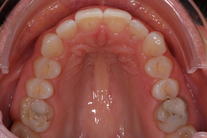

40-årig kvinna som tycker att de två framtänderna står ut framför alla andra tänder. Behandlingen bestod av 11 månader med genomskinliga Invisalignskenor.